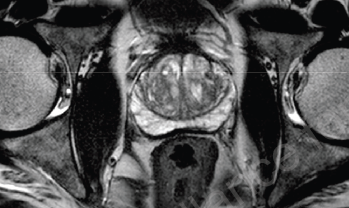

New research provides further support for European moves to ensure that prostate biopsies are guided by MRI scans rather than standard ultrasound. It finds that the use of pre-biopsy MRI combined with targeted prostate biopsy is better than a biopsy alone in detecting prostate cancers that are likely to need treatment.

The research was published in JAMA Network Open, led by the National Institute for Health Research (NIHR) and the Universities of Bristol, Ottawa, Exeter and Oxford. The systematic review combined the results from seven studies covering 2,582 patients, focusing on men who had not had a prostate biopsy before.